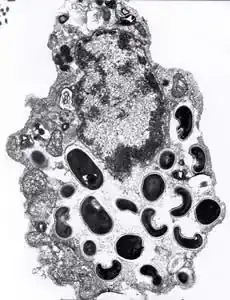

Encephalitozoon intestinalis is a parasite.[1] It can cause microsporidiosis.[2]

Microsporidia are obligate intracellular opportunistic fungi that cause significant pathology in immunocompromised (simply put: having an impaired immune system) hosts. Like other obligate intracellular pathogens, microsporidia exert significant stress on infected host cells. Microsporidia infection alters host cell cycle regulation and can lead to development of multinucleated host cells.